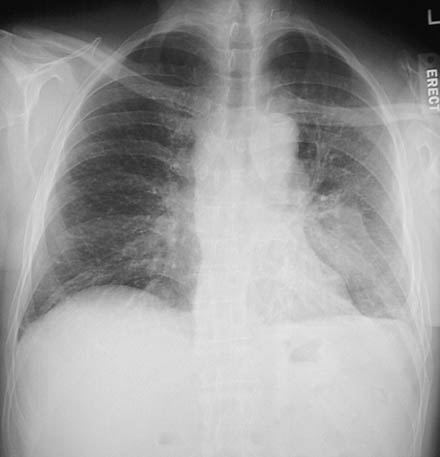

The chest radiograph above in PA view and lateral view below demonstrate a diffuse reticular and nodular pattern of involvement by metastatic carcinoma spreading into the lymphatic channels of the lung.